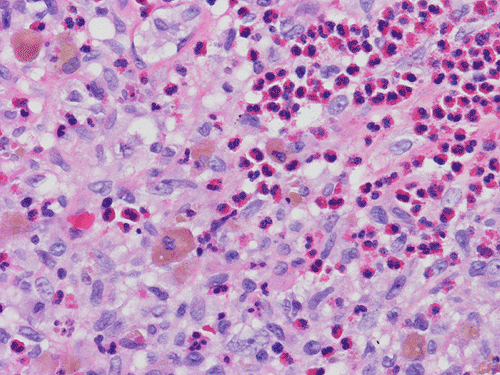

At scanning magnification (Panel A), the lung parenchyma is replaced by some coalescing fibrous nodules. The degree of involvement is variable at different fragments (Panel B and C). In the less affected areas, there are some fibrotic thickening of the septa (Panel C). In some areas, the changes are minimal and the pleural appear to be uninvolved (Panel D and E). In low to medium magnifications, these nodules of fibrosis contains a large number of hemosiderin laden macrophages (Panel F and G) admixed with fibrous tissue. The diagnostic tissue, however, is present in areas with increased cellularity. In these areas, there is a background of cells with a moderate amount of cytoplasm and bland nuclei. Some of these nuclei have kidney shape (arrow in Panel H). In some areas, many of the nuclei have a deep nuclear groove that resemble a coffee bean (arrow in Panel I). In the third type of areas, the nuclear grooving is not distinct (Panel J). Prominent eosinophilic infiltrations are almost always present. Immunohistochemistry on CD1a revealed many positive cells (Panel L). Also present in the specimen are multiple small blood vessels with thickened intima (Panel K). A Movat pentachrome stain demonstrates an internal elastic layer in these vessels and confirms that these are arteries (Panel M and N).

Histopathologic signature of Langerhans cell histiocytosis, namely kidney shaped or coffee bean shaped, bland nuclei associated with eosinophilic infiltration is not difficult to see in most of the cases. The amount of eosinophilic infiltration and the proportion of cells with nuclear grooving, however, can be quite variable but this problem can usually be overcome by a diligent search. Demonstration of CD1a by immuhonistochemistry or Birbeck granules by electron microscopy will confirm the diagnosis.

Pathologically, PLCH can be broadly divided into an early or cellular stage and a late or fibrotic stage. Demonstration of LCs is of critical importance for a correct diagnosis. The morphology of LCs is similar to LCH in other organs. LCs are characterized by a deep nuclear groove which lead to “coffee bean-shaped” or “kidney-shaped” nuclei. In most cases, the level of atypia and pleomorphism is low. A moderate amount of amphophilic to weakly eosinophilic cytoplasm is present. The cytoplasmic membrane is indistinct. Eosinophils and chronic inflammatory cells, varying from scant to abundant, are present. Except for a scant frankly pleomorphic cases, the level of pleomorphism and atypia is minimal to low. Eosinophilic abscesses with central necrosis may be present. Immunohistochemically, LCs are similar to their normal counter parts and are positive for CD1a and S100. At the ultrastructural level, Birbeck granules can be demonstrated. For most cases, the diagnosis can be established by histopathologic criteria but these additional features help to confirm the diagnosis.

In the early stage of PLCH, there are interstitial infiltrates composed of LCs, lymphocytes, macrophages, eosinophils, plasma cells and fibroblasts 4. The infiltrates enlarge to form nodules centered on the small airways. Brown pigmented macrophages (smokers macrophages) are present in and around the nodules. Eosinophils tend to localize at the innermost layer of the nodules, where LCs can be most easily found in the thickened interstitium. Associated patchy interstitial and airspace organization or respiratory bronchiolitis may be present. Other smoking related changes are also common. Cavitation often occurs within the nodules which represents either an airway remenant or de novo cavitation as the inflammatory infiltrate enlarges. There is centripetal replacement of the nodules by fibroblasts which produce the classic stellate lesions of PLCH. As the disease progresses, the number of nodules, cavitary granulomas and fibrotic scars increase in number.